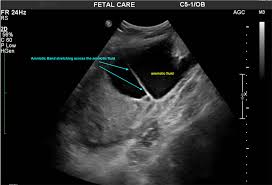

Amniotic band syndrome can occur when the inner layer of the placenta called the amnion is damaged during pregnancy. Amniotic band syndrome is a rare congenital disorder that occurs when parts of a fetus are entangled by fibrous strands of the amniotic sac. Amniotic Band Syndrome can cause a number of different birth defects depending on which body part s is affected.

These fiber-like bands tangle around the developing fetus restricting blood flow thus affecting the growth of certain body parts. Most of the time the bands wrap around an arm leg fingers or toes. This rupture occurs randomly and is not related to anything a mom did or did not do during pregnancy.

Amniotic band syndrome also known as constriction ring syndrome happens when fibrous bands of the amniotic sac the lining inside the uterus that contains a fetus get tangled around a developing fetus. The amniotic band syndrome can be treated and managed in the following ways. If this happens thin strands of tissue amniotic bands form inside the amnion.

Amniotic band syndrome happens when the amniotic sac ruptures this is what releases the bands into the amniotic fluid which then attach to the baby. Minimal diagnostic criteria consist of.